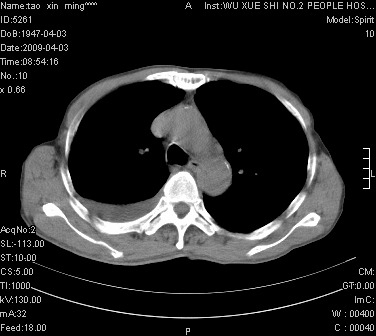

男.62.咯血.胸痛

是不是外伤的,看起来右侧肋骨骨折,右肺唑伤,右胸腔积血, 右肺背段可见一软组织肿块,边缘清晰,可以和中中央型肺ca合并

明天请武大中南医院外科熊主任手术.患者无外伤.我考虑肺癌

1)考虑右肺下叶周围型肺癌,并右肺下叶肺出血。2)右侧少量胸腔积液。

1)考虑右肺下叶周围型肺癌。2)右侧少量胸腔积液。